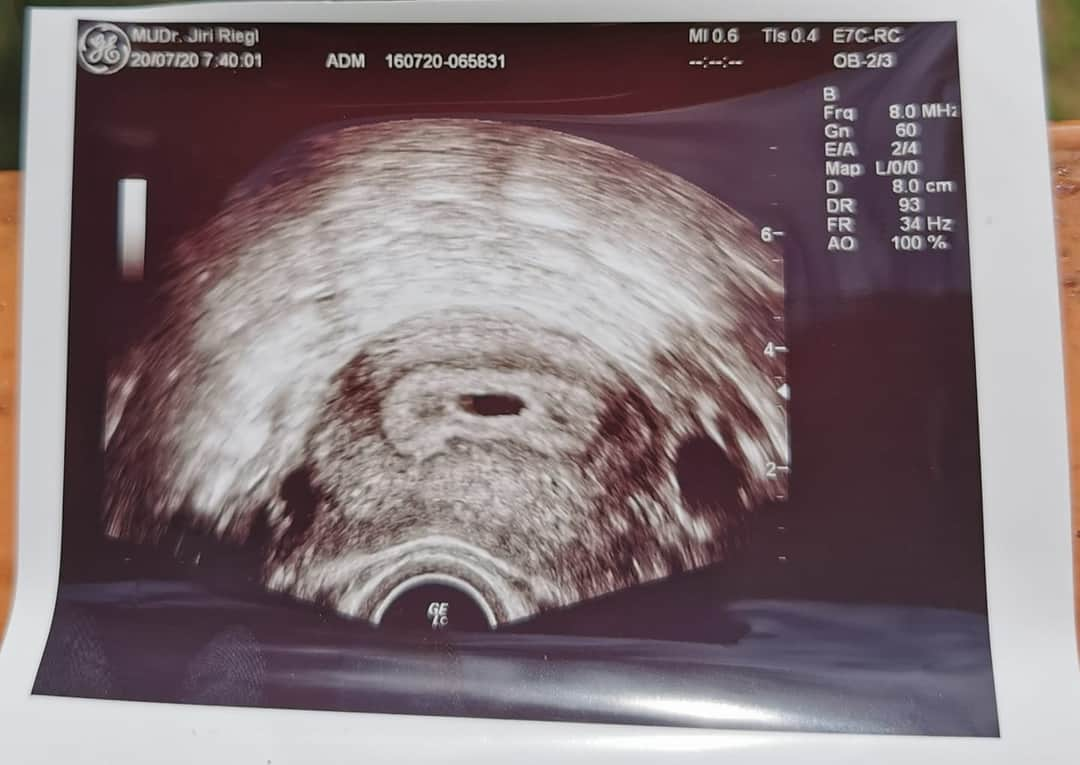

Zdravím holky, chtěla bych vás moc poprosit o radu, vaši podobnou zkušenost. Poslední MS byla 16.6... 17.7 jsem jsi udělala Těhotenský test byli jasně viditelné // 20.7 fotka z ultrazvuku. A teď důvod strachu který mam. Doktor řekl jednu větu která mě znervózněla a od té doby hledám na internetu vše možné a nemožné... Prohlásil že tam není vidět a tudíž budeme ve vašem případě doufat... Další kontrola za měsíc tedy 18.8 a i když se kontrola blíží jsem čím dál víc nervóznější a vyděšená aby to nebylo zamkle těhu.. 😟 moc děkuji za vaše názory

právě vůbec nevím co by mělo být vidět je to moje první těhu já byla šťastná když viděla tohle dokud právě neřekl danou větu která mě absolutně vyděsila a rozhodlila..

Co by mělo být 20.7. vidět? Teprve teď jdeš na kontrolu, kde by mělo být něco pořádněji vidět.